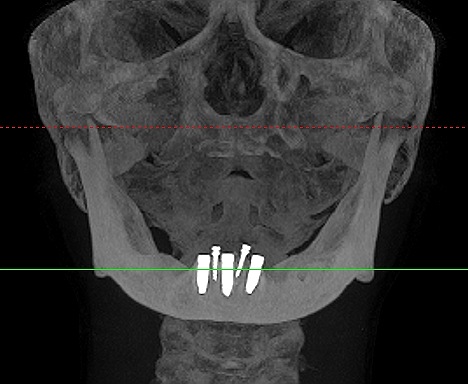

インプラント埋入時になります

3本とも4mmの13mmというインプラントを埋入

術前術後のパノラマになります

インプラントはオペ時に5本入れていることになります